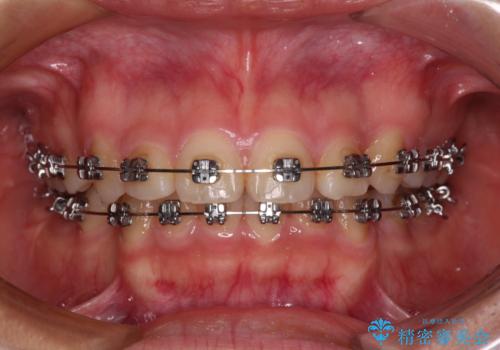

- メタルブラケット

上下ともに歯列が前方に突出していたため、上下左右の第一小臼歯4本を抜去する方針(既に上顎は抜歯されています)で、ワイヤー装置による矯正治療を行うこととしました。

舌の突出癖があり、咬合力も強かったため、治療期間は長くなることが懸念されましたが、舌のトレーニングをしっかりと行っていただいたこともあり、2年弱で治療を終えることができました。